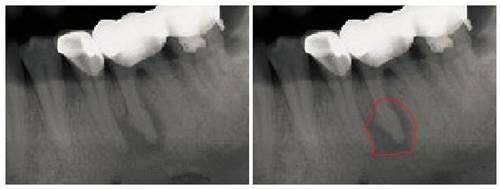

不拍X光,无法发现牙根周围这么大的慢性脓肿

(3个白色连起来的“帽子”是烤瓷牙,下同)